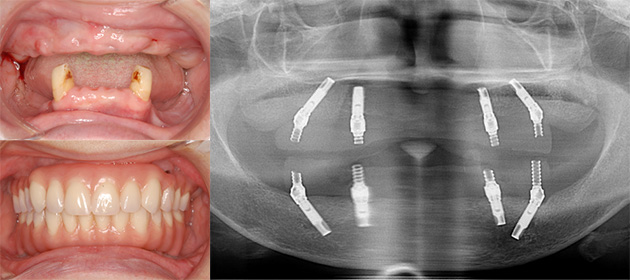

All-on-4 (6)の治療例

取り外しの入れ歯を入れたくない